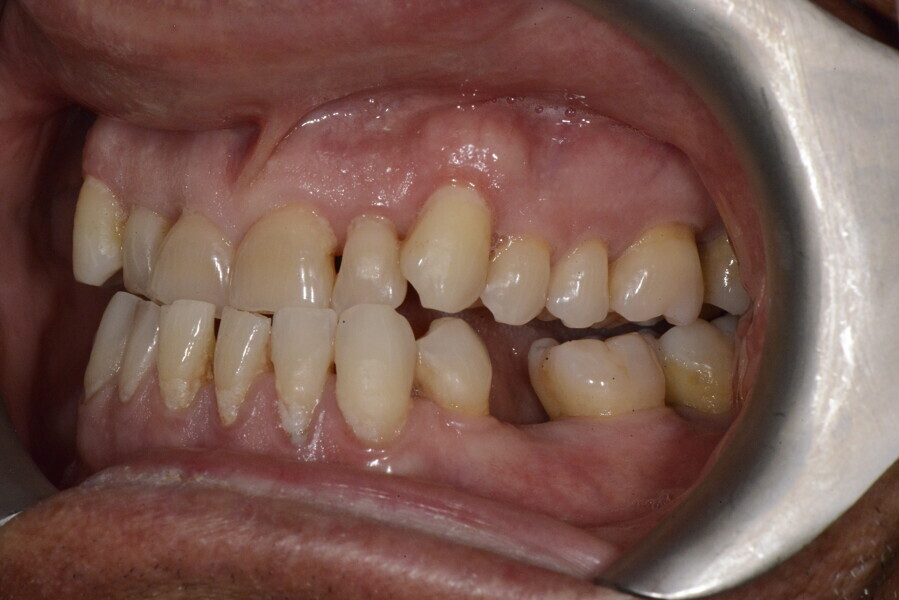

The 58-year-old patient wished to improve his oral aesthetics and function, complaining of mobility of the posterior teeth and wear of the anterior teeth. After data collection, a very complex situation was identified (Figs. 11–13):

1. severe periodontitis with poor prognosis of some teeth;

2. anterior crossbite;

3. severe wear mainly of the anterior teeth and compensatory eruption;38

4. atypical swallowing and lower posture of the tongue at rest;

5. masticatory dysfunction during the mastication test; and

6. no significant signs of temporomandibular disorder.

After the first phase of aligner treatment, we had achieved better inter-arch coherence, better maxillary arch expansion, and some space for improving the anterior tooth proportions restoratively (Fig. 19). We then temporarily restored the anterior teeth directly with composite, closing the spaces, improving the tooth proportions and further increasing the maxillary arch expansion (Fig. 20). We used restorative arch expansion to reduce the orthodontic destabilisation of the teeth to achieve the correct inter-arch coherence and retain the teeth in the cortical bone.38 A refinement aligner phase was undertaken to improve the final alignment of the gingival zenith and to improve the inter-arch coherence (Fig. 21). The periods of the first orthodontic phase and of the refinement were used to augment the mandibular and maxillary bone and to place the implants (Fig. 22). At the end of the orthodontic treatment, the case was finalised with ceramic veneers in the anterior area and temporary restorations on the implants in the posterior area (Figs. 23–26).